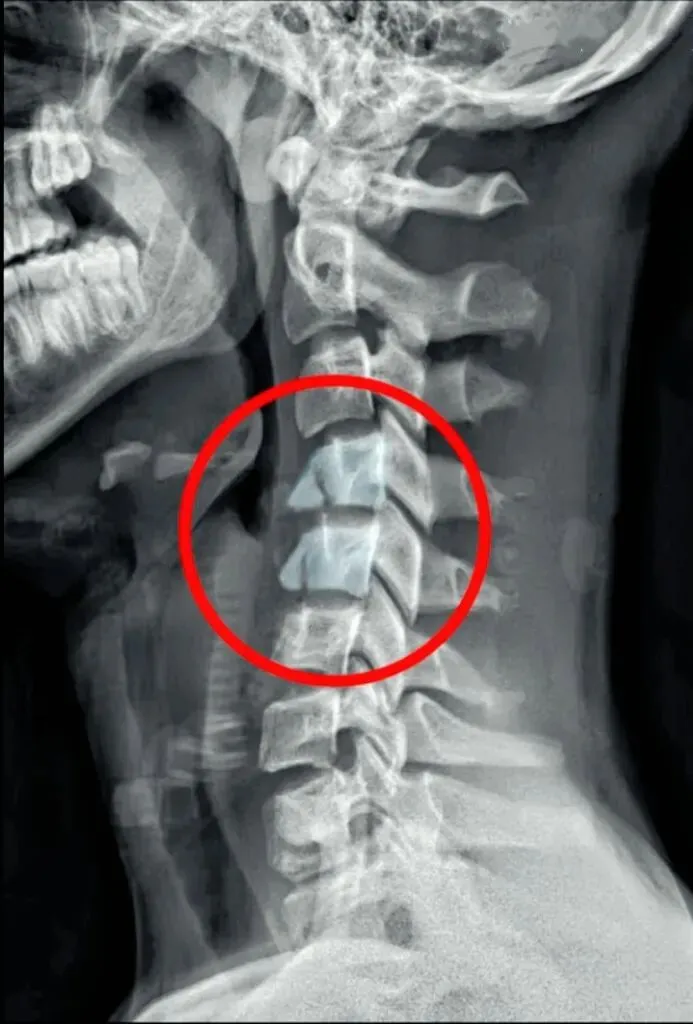

一骨是是我们主要在颈椎侧位X线片中观察椎体的形态与结构,查看椎体是否规则,

椎体边缘有无变尖或呈唇样改变的骨质增生。

椎体骨质有无破坏,密度是否正常,如肿瘤或者感染。

椎体的高度是否均匀,有无压缩变形。椎体高度减小可能提示骨质疏松、压缩性骨折

或椎体的发育异常等。